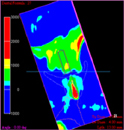

骨質のカラー表示

ハンスフィールドユニット(CT値)によって骨質が診断可能

各2D断面をMischの分類(1993)に応じてカラーリング表示。インプラント断面を回転させながらドリル方向に沿った骨質診断を行い、安全かつ骨密度の高い位置への埋入シミュレーションが可能になります。